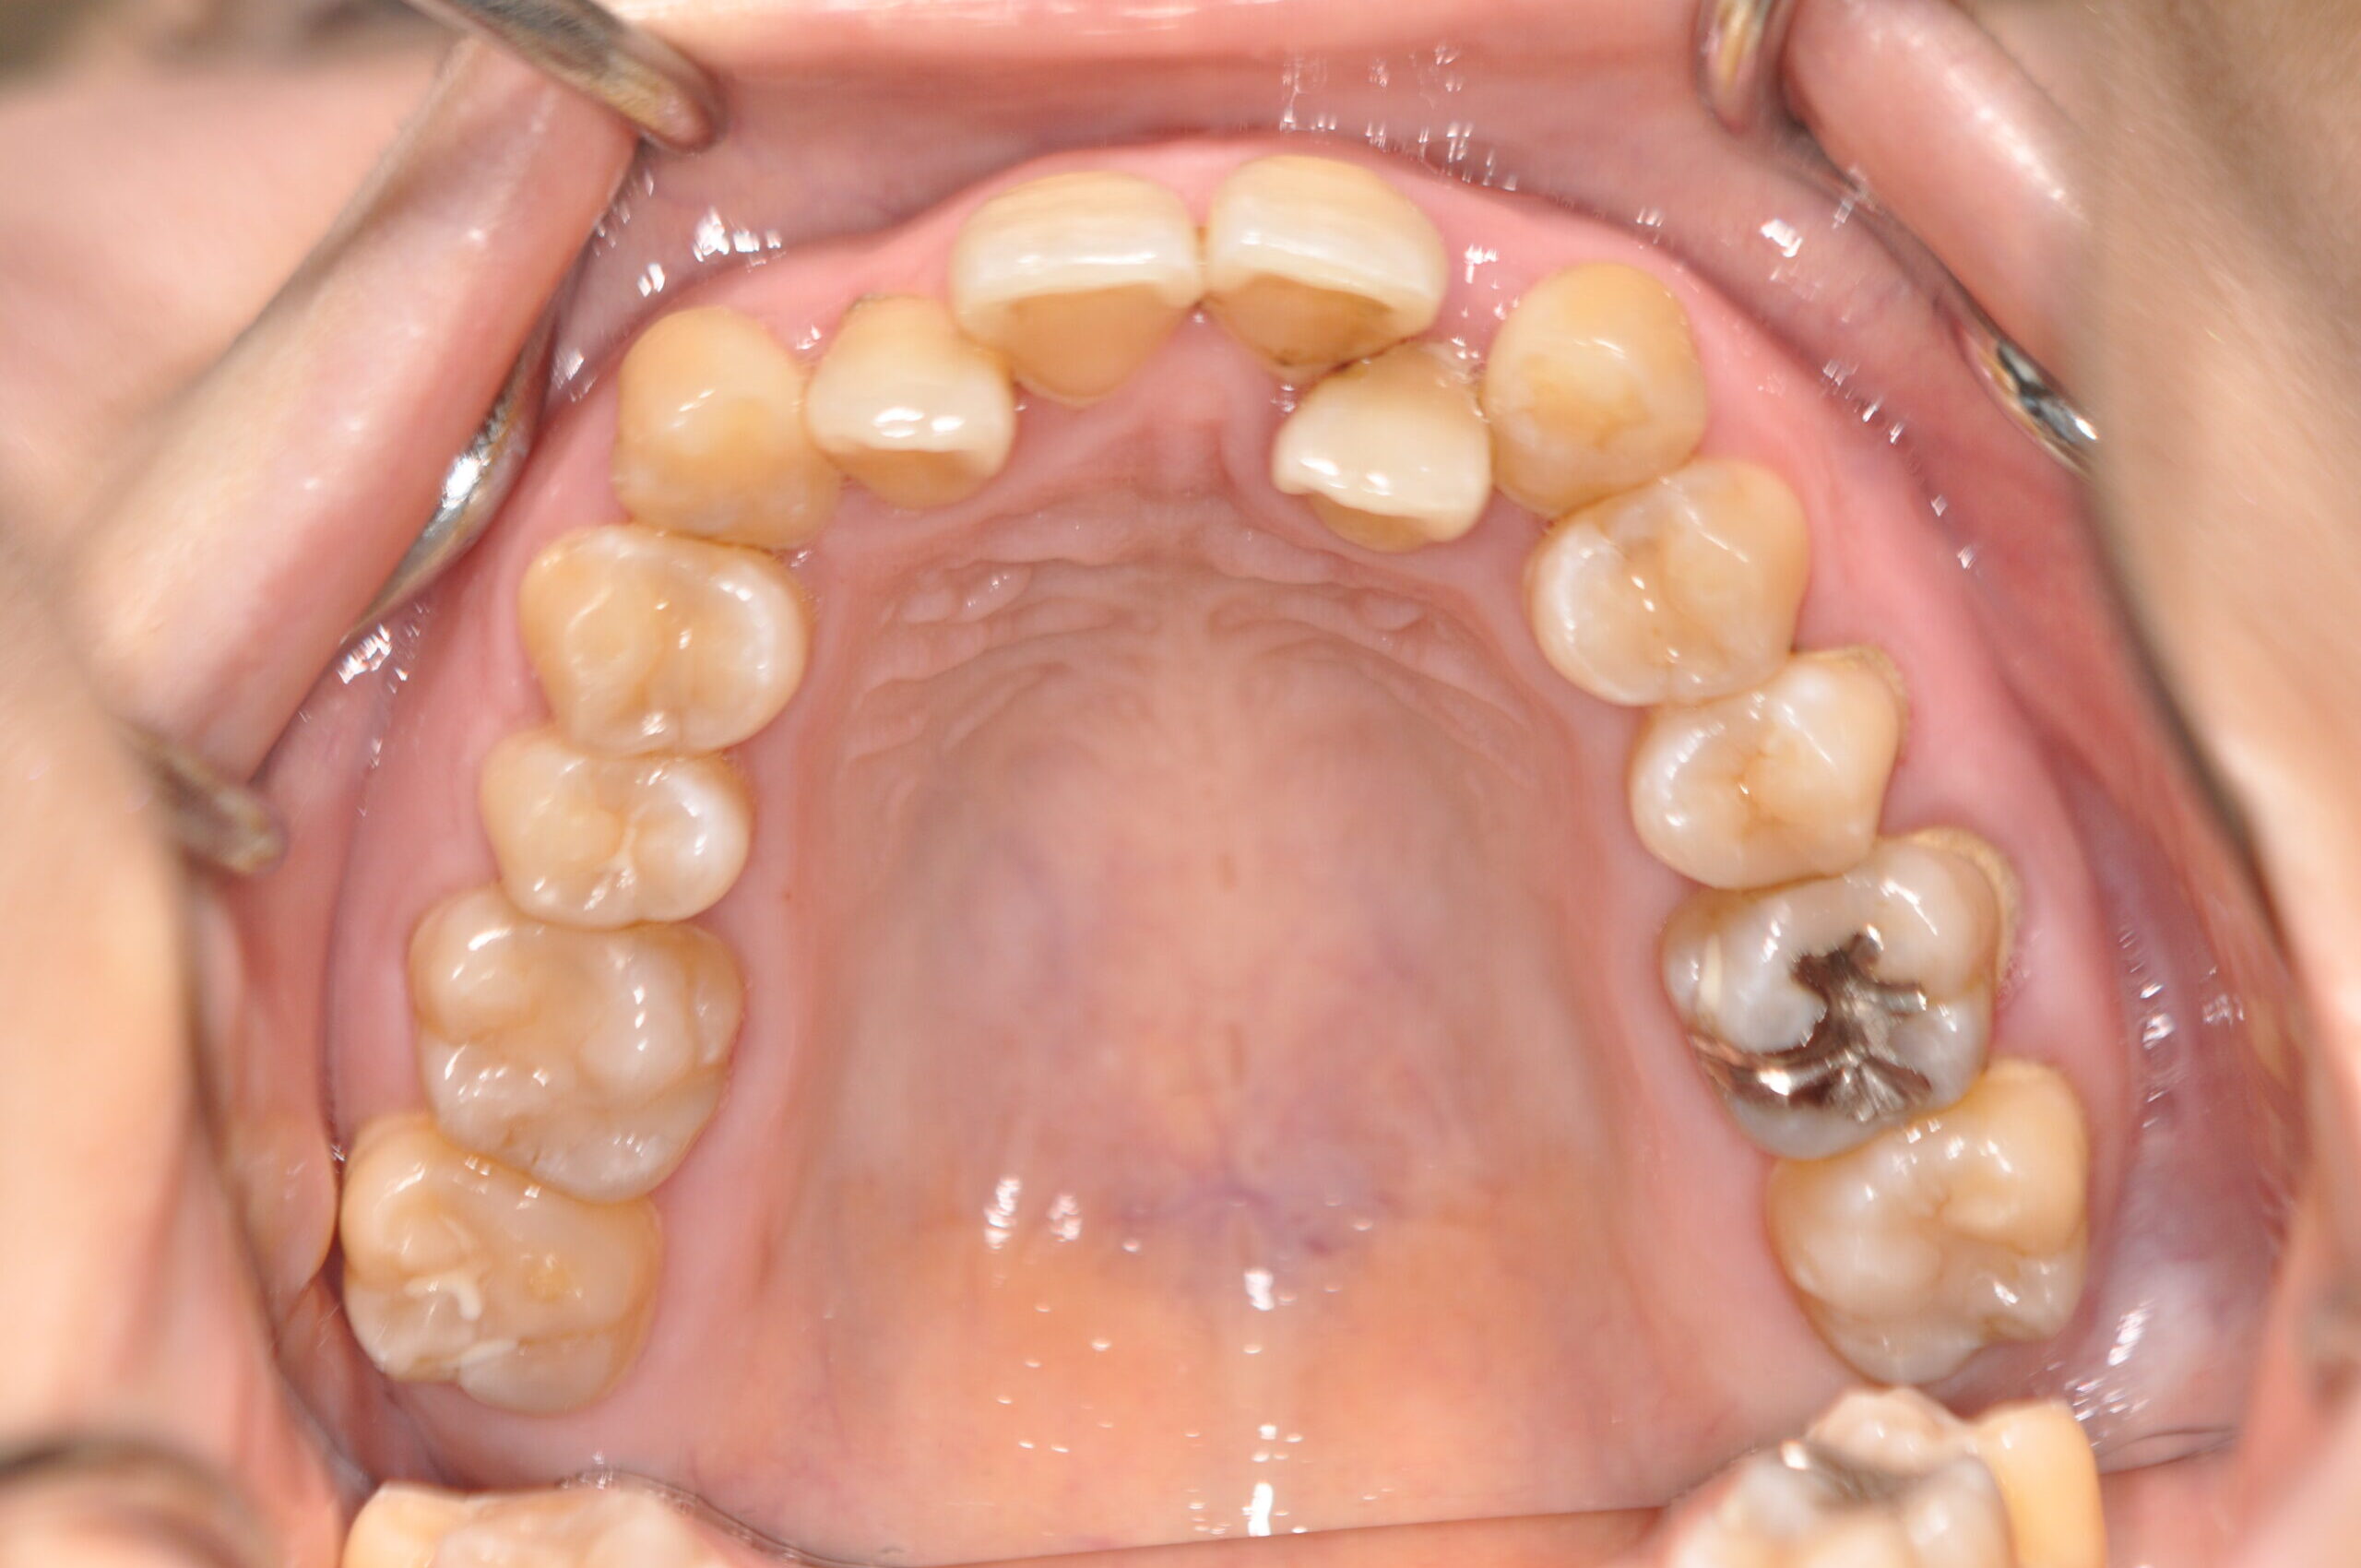

動的治療終了時

症例 症例 症例 症例 症例